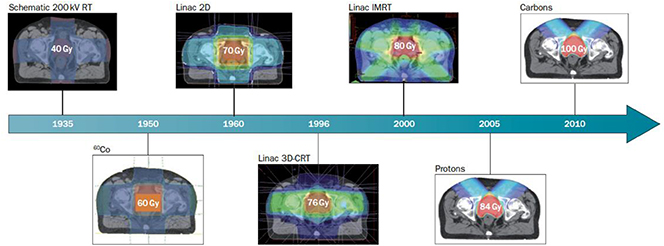

5.2.1. Motivation to use and expand x-rays and particle therapy

The use of x-rays in radiotherapy (RT) is now the most common method of RT for cancer treatment. While x-ray therapy is a mature technology there is room for improvement. The current challenges are related to the accurate delivery of x-rays to tumours involving sophisticated techniques to combine imaging and therapy. In particular, the ability to achieve better definition and efficiency in 4D reconstruction (3D over time) distinguishing volumes of functional biological significance. Further technical improvements to reduce the risk of a treatment differs from the prescription and moving towards 'personalised treatment planing' are being made. Some of these techniques such as: image-guided radiation therapy (IGRT), control of the dose administered to the patient (in vivo dosimetry) or adaptive RT to take into account the morphology changes in the patient, are the state of the art and are being implemented in the routine operation of these types of facilities. An example is the so-called MR linac, which provides magnetic resonance (MR) and RT treatment at the same time. Finally, the reduction of the accelerator costs and the increase of reliability/availability in challenging environments are also important research challenges to expand this kind of RT in low- and middle-income countries (LMICs).

Proton and ion beam therapy has growing potential in dealing with difficult-to-treat tumours, for example, because of the risk of damaging neighbouring sensitive tissues such as the brainstem or visual nerves in the case of head tumour treatments. Also, some treatments may benefit from the use of particles that deliver doses with greater radiobiological effectiveness (RBE) and higher local precision, notably carbon, and in the near future also helium ions.

In the last three decades about 25 proton and 4 hadron therapy facilities were built in Europe (figure 5.6). But only a few more are actually under planning or construction, among them only one hadron facility project (SEEIIST 1 ). Thus, new efforts are required to make these techniques smaller, cheaper (in investment and operating costs), and easier to maintain, which will be discussed in a separate chapter below showing potentials for the next three decades.